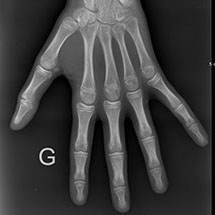

Elle peut être réalisée sur tout le corps et permet avant tout l’étude des os,

Pour les os et articulations : des fractures, de l’arthrose, des malformations

Elle utilise les rayons X, consistant à impressionner un film qui sera plus ou moins noirci selon l’organe radiographié : ainsi les os apparaîtront blancs et l’air noir ; les tissus mous seront de différentes nuances de gris.

Dans notre cabinet, la technique est numérisée et la surface sensible est en fait un capteur et non un film, ce qui permet de modifier le contraste après avoir pris le cliché et d’agrandir certaines zones pour mieux voir.